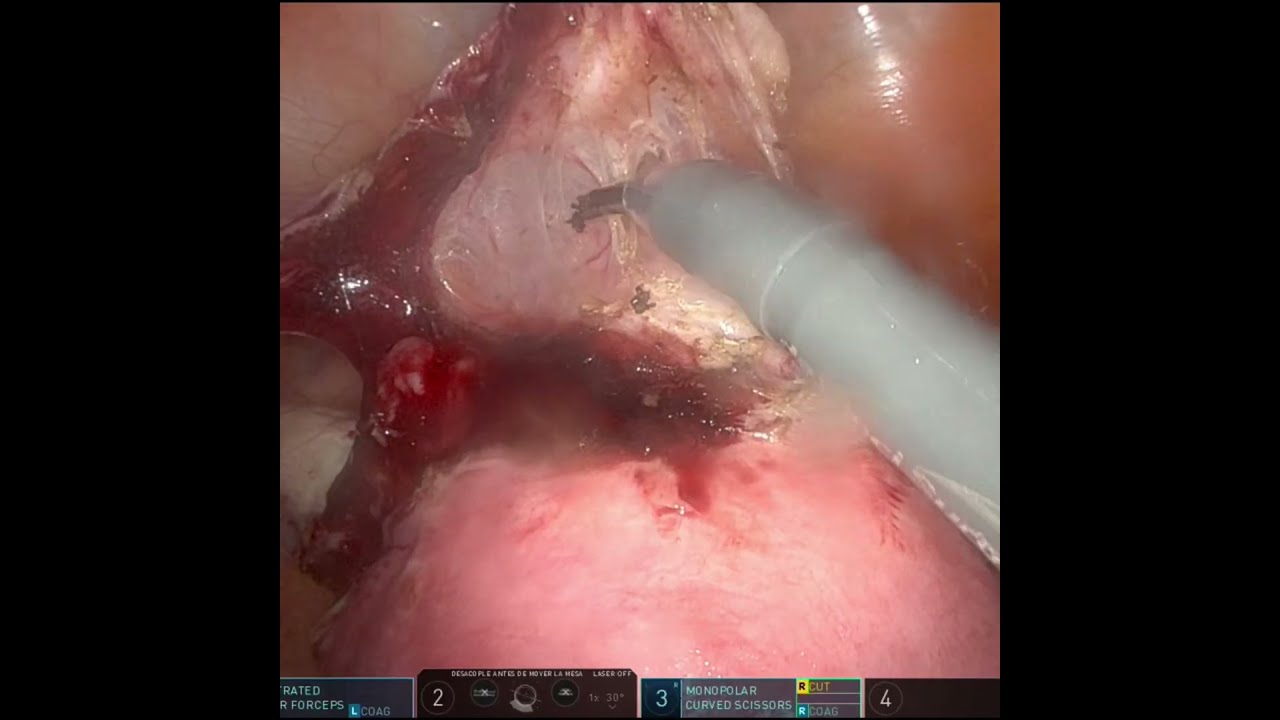

Cirugía Robótica Ginecológica

Histerectomía por laparoscopia

Cirugía por cáncer de endometrio

Cirugía por cáncer de ovario